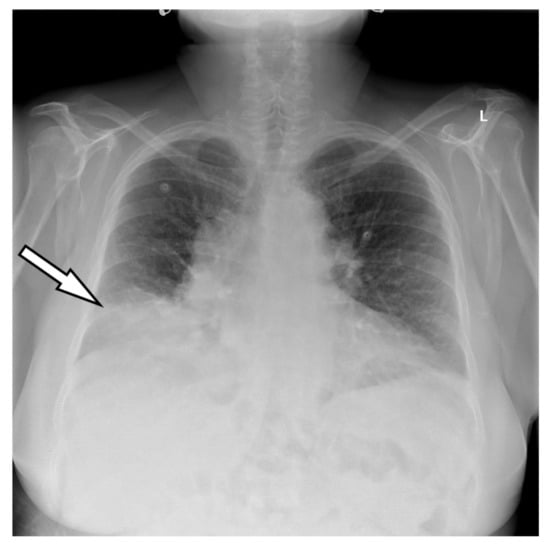

2. Case Presentation